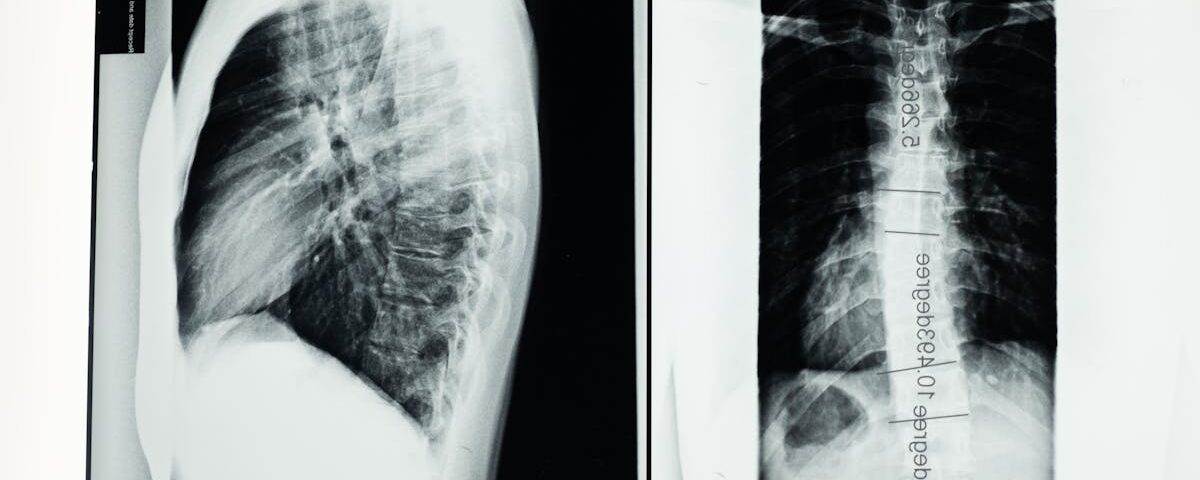

Avant d’entamer un traitement de décompression neurovertébrale, il est essentiel de consulter un professionnel de santé qualifié. Cette première étape comprend une évaluation approfondie de l’état de santé du senior, notamment l’examen de l’historique médical, des douleurs ressenties et des résultats d’imageries si nécessaires. Cela permet de déterminer l’adéquation du traitement et d’exclure d’éventuelles contre-indications.

Quels examens permettent de diagnostiquer un bombement discal?

Une IRM ou une radiographie sont les outils les plus couramment utilisés pour diagnostiquer un bombement discal.